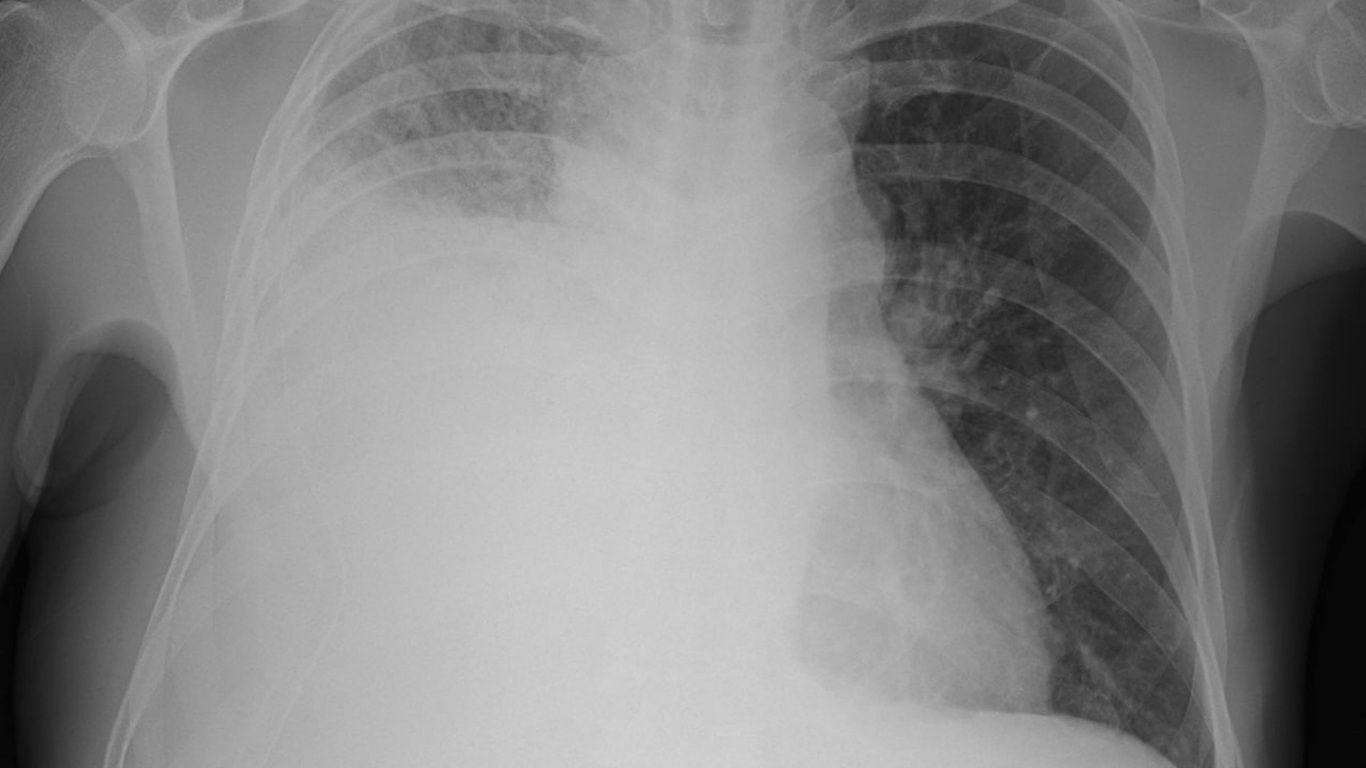

4.2. Hình ảnh học

X-quang ngực: thấy hình mờ dạng xơ ở vùng màng phổi, góc sườn hoành tù hoặc mất.